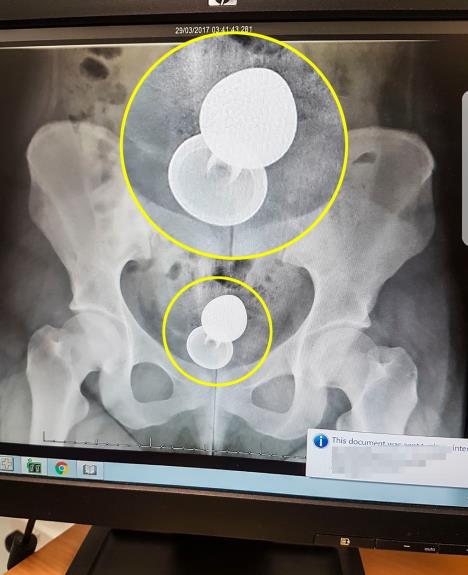

Devojka je pokušala sama da izvadi seks igračku ali kada nije uspela, dečko joj je predložio da ga ostavi, jer će sama izaći napolje. Potom joj je rekao da mora rano ujutru da ustane za posao, pa je otišao. Zabrinuti prijatelj ju je odveo u bolnicu, a lekari su upozorili Emili da je postojala opasnost po njena creva zbog oštrih ivica igračke. Na rendgenskom snimku se jasno videlo u kolikoj je opasnosti Emili bila.

"Nisam htela naglas da pričam o tome, pa sam tražila olovku i papir. Sestra na recepciji mi je rekla da se to dešava često i rekla mi je da je čula i gore stvari", kaže ona. Istakla je da je bila jako uplašena i da je prvo mislila da će doktori moći ručno da izvade igračku. Tek kada je videla rendgenski snimak shvatila je da to neće ići tako lako.

29. marta Emili je imala jednosatnu operaciju, koja je uključivala postavljanje kamera u nju da bi igračku izvukli napolje.